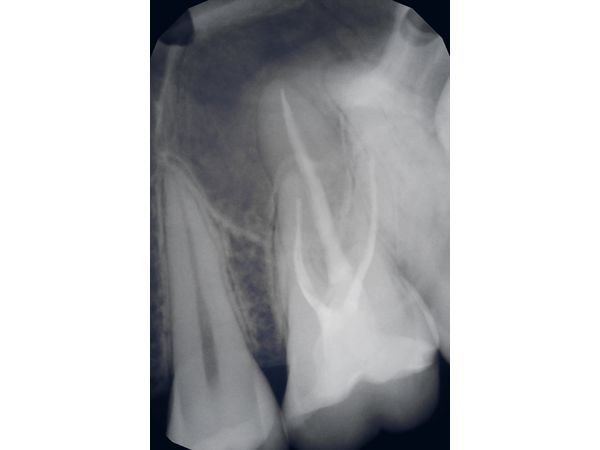

- измерили длину каналов апекслокатором и сделали рентген для контроля;

- запломбировали каналы гуттаперчевыми штифтами и пастой АН+;

- проверили однородность пломбировочного материала и длину с помощью рентгена;